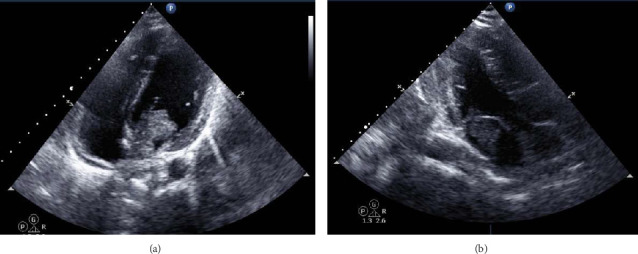

Cardiac myxoma is considered the most common primary cardiac tumor and has been reported to cause different neurological complications through distinctive mechanisms, including pseudovasculitis. Herein, we present and review a case of a young male with a previous history of ischemic stroke who presented with multiple territorial ischemic insults in the presence of a presumed diagnosis of vasculitis. Once further workup was done, he was found to have a left atrial myxoma.